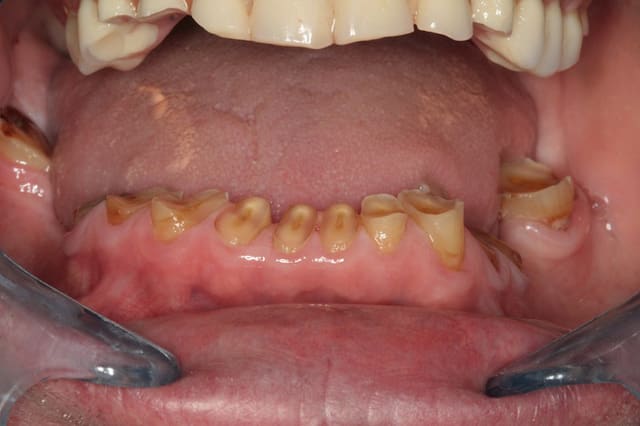

ça aura été une longue journée, pas eu le temps de peaufiner occlusion ou de polir partout bien comme il faut, j'y reviendrais

première impression sympa pour le grand changement

les points de contacts étaient bon, et j'ai pu en retoucher 3 en adjonction pour avoir un truc bien partout

par contre niveau occlusion des dents haut/bas, je suis moins sur, je pense qu'on aurait pu faire mieux, je pourrais regarder tranquillement quand il reviendra, et éventuellement ajuster un peu si besoin

Photo 2 superbe !

Photo 4 ? tu n'as pas recouvert la partie vestibulaire de 13 a 23 ?

Tu avais tester l'occlusion sur des provisoires ? si oui combien de temps ?

et non, le patient est prévenu qu'on peut faire des facettes plus tard si on veut faire quelque chose de joli

cela dit c'est vrai que dans ce cas, on aurait peut être pu insérer des faces vestibulaires tellement c'était usé au départ

pas de provisoires, juste la gouttière, on en avait parlé